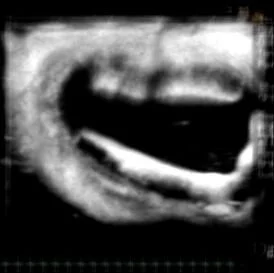

![[Uterus] Averaged](https://images.squarespace-cdn.com/content/v1/68926c61b505126b7e78f27f/820ef7c0-c90c-47db-b701-7bd3053a6adf/uterusaveraged-otherfocus-web.jpg)

[Uterus] Averaged